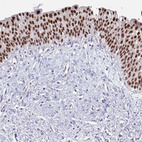

Immunohistochemistry analysis in human prostate and endometrium tissues using HPA050505 antibody. Corresponding FOXA1 RNA-seq data are presented for the same tissues.